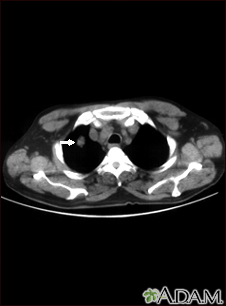

TC que muestra una sola lesión (nódulo pulmonar) en el pulmón derecha. Se puede ver el nódulo como un círculo claro en la parte superior del área oscura, al lado izquierdo de la imagen. Un pulmón normal aparecería completamente negro en una tomografía computarizada.